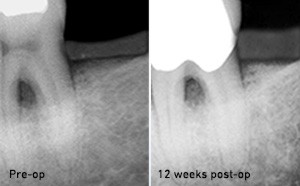

Parodontologie

Plus de confort pour le patient avec un traitement indolore et d'excellents résultats post-opératoires, y compris la guérison et la croissance accélérées des tissus sains.